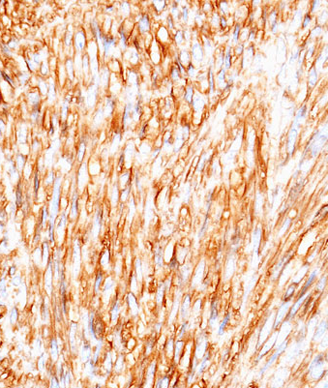

Histopathologic image of GIST arising in the stomach; CD34 immunostain